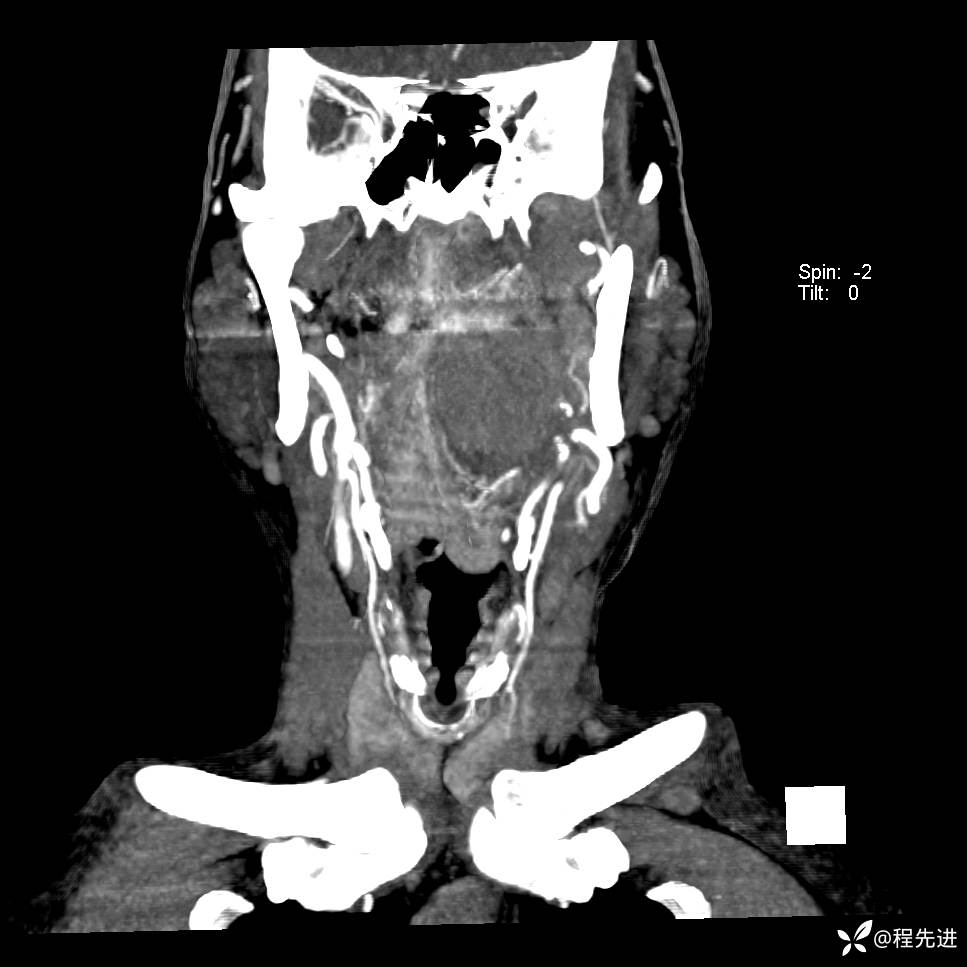

增强冠矢状位重建:

CTA: